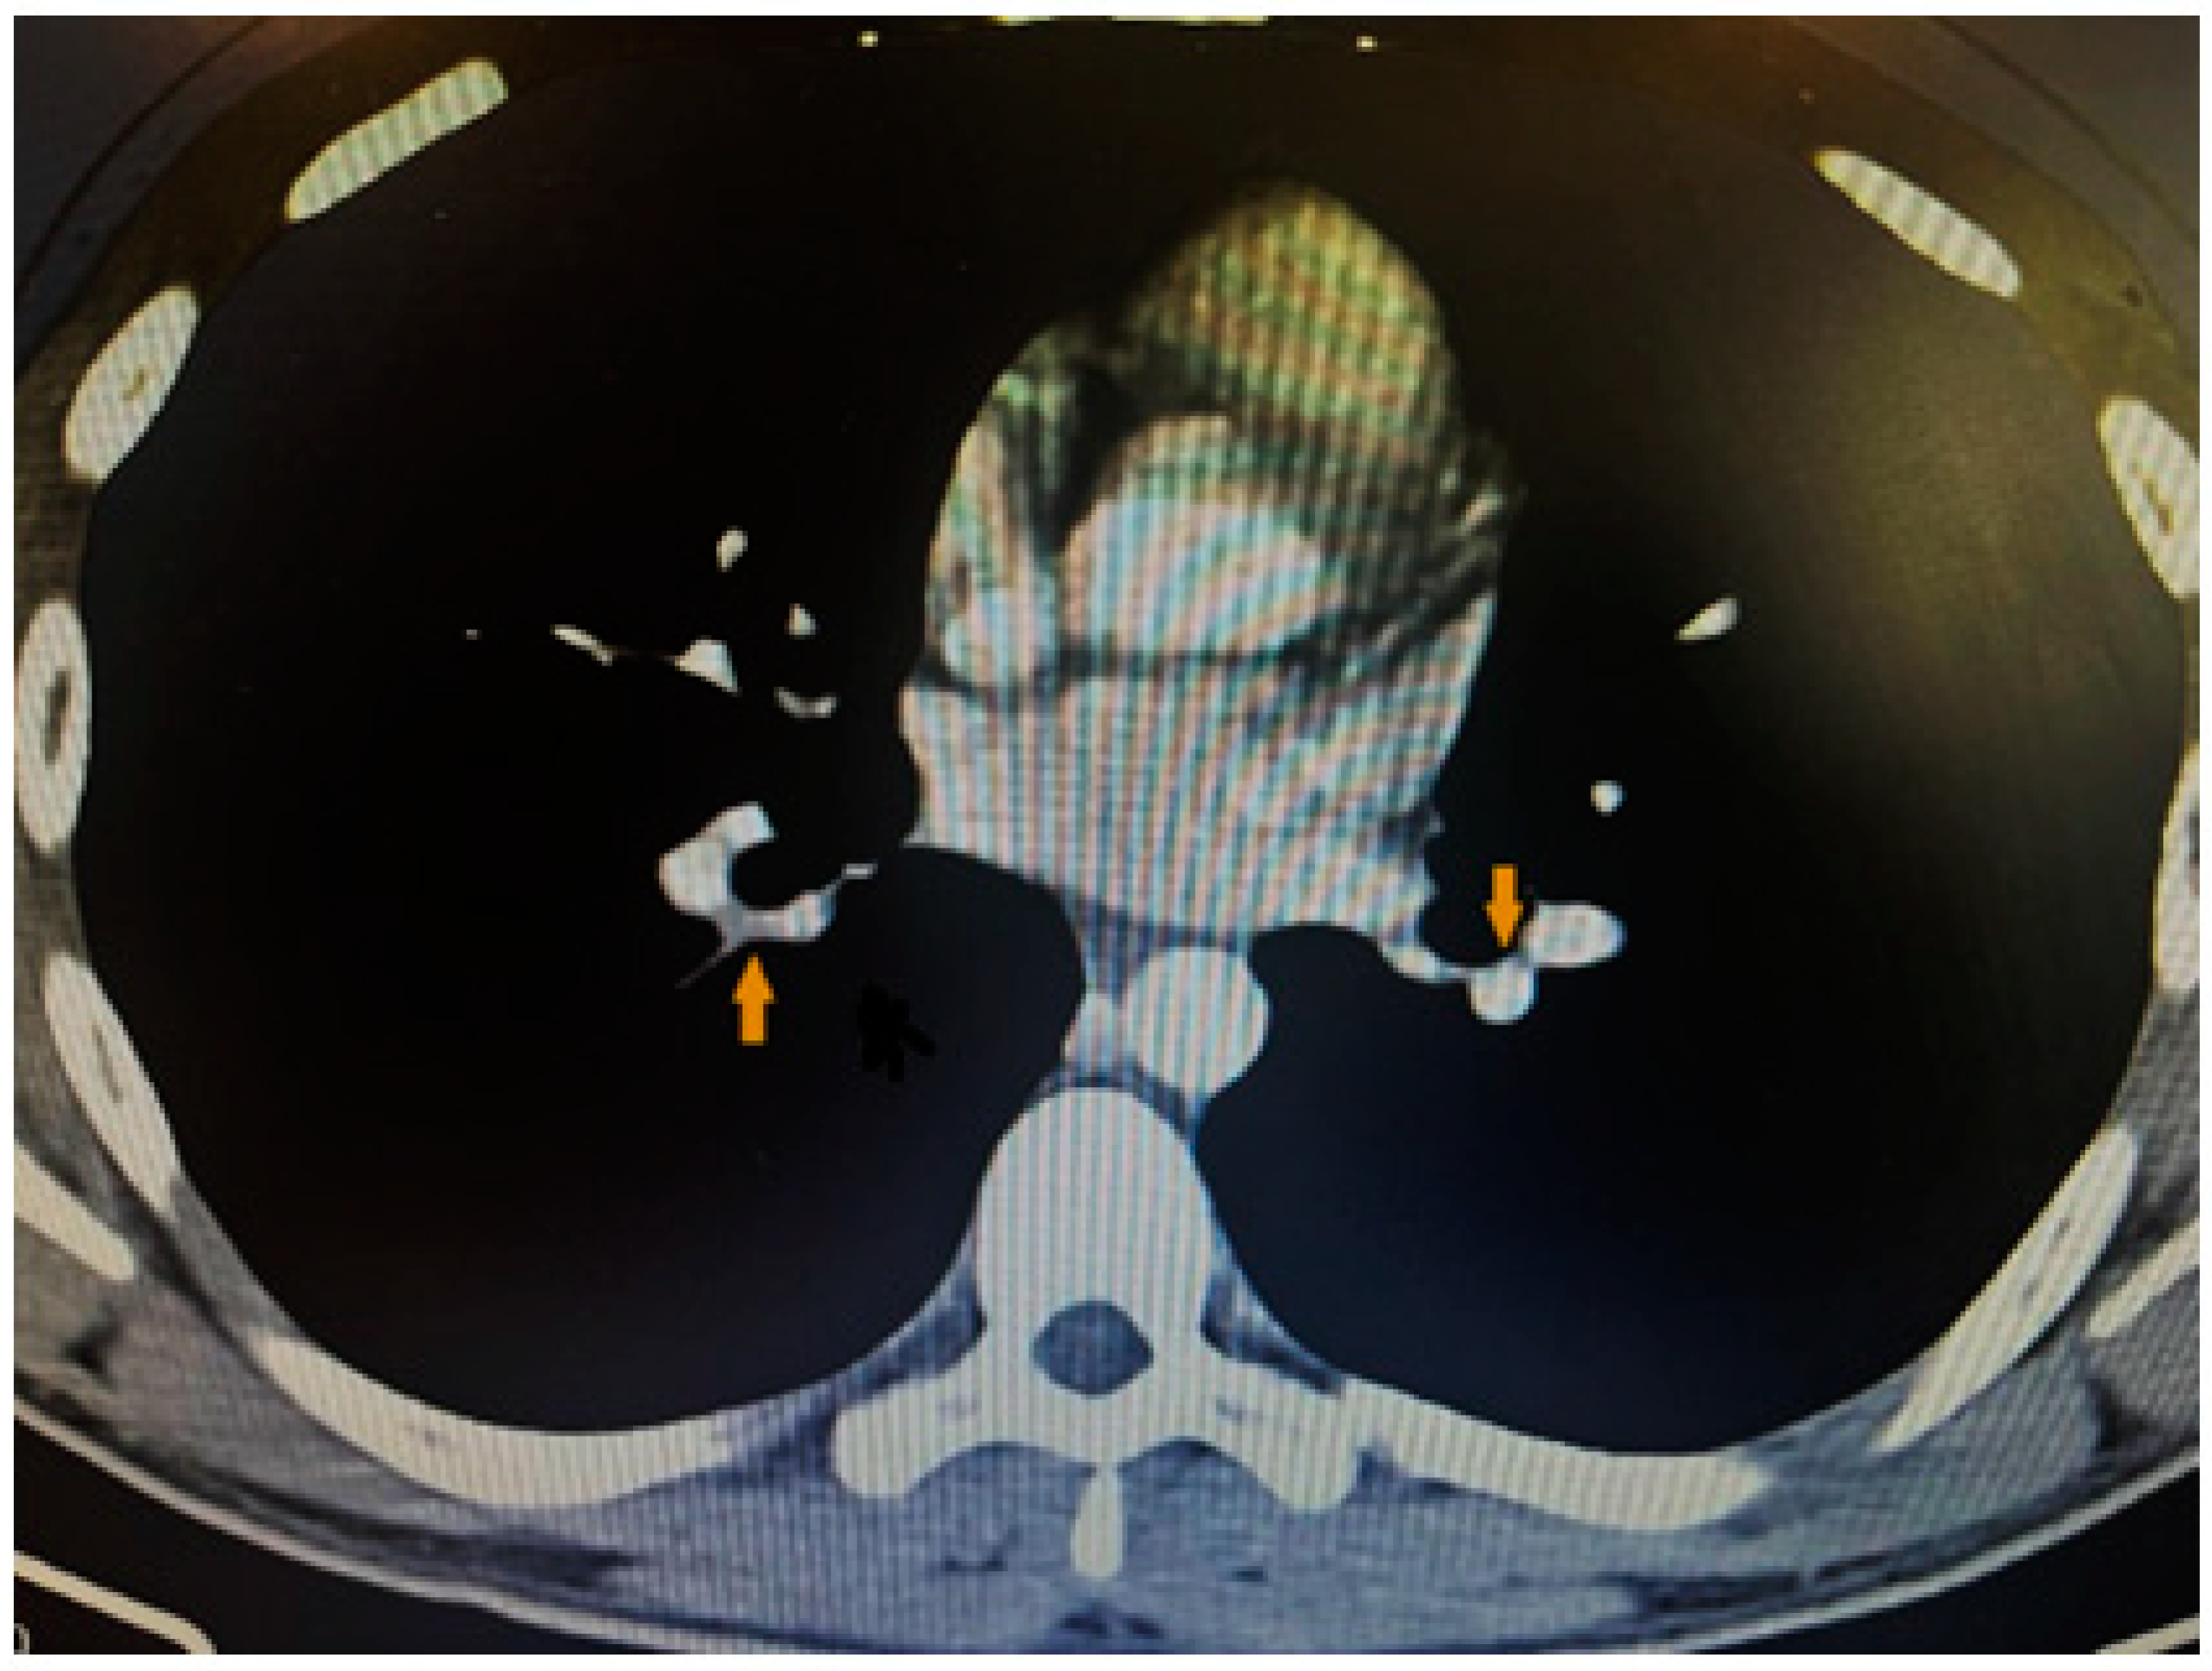

2. Case Presentation